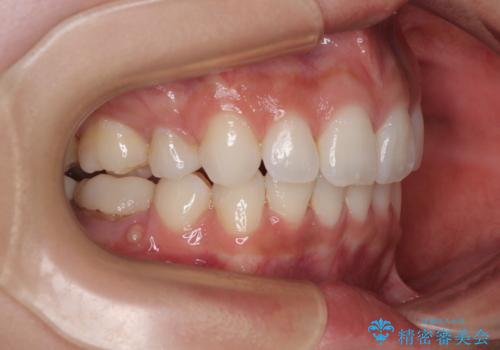

右下の埋伏歯はやはり癒着しており、抜歯の後にインプラントを埋入することとなりました。

埋伏歯の牽引や、奥歯の咬み合わせ改善、インプラント補綴治療と治療期間が延びてしまう要素が多く、治療は難航しましたが、最終的に非常に満足のいく仕上がりとなりました。